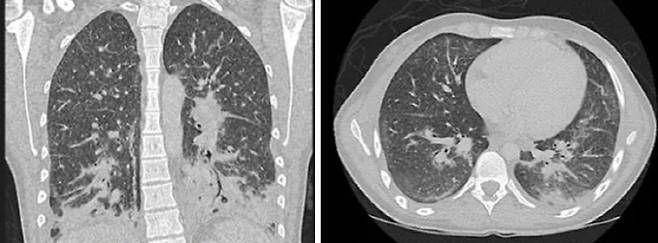

[스포츠조선 장종호 기자] 한 달간 액상 전자담배를 피운 19세 여성의 폐가 '산산조각 난 유리'처럼 보여 충격을 주고 있다.

이 여성은 1주일 동안 호흡곤란, 오한, 기침, 고열 등의 증상을 보여 응급실을 찾았다,

의료진은 흉부 CT 촬영 결과, 폐에 '간유리음영(ground glass opacity, GGO)'이 나타난 것을 확인하고 세균성 폐렴으로 초기 진단했다.

간유리음영 또는 간유리결절은 흉부 CT에서 폐에 뿌옇게 보이는 부분을 말한다. 마치 모래 등을 이용해 투명한 유리를 갈았을 때 표면이 뿌옇게 변하는 것을 '간유리'라고 부르는 데서 유래했다.

그러다 환자가 지난 한 달 동안 남자친구의 전자담배를 사용했다고 말한 후에야 의사들은 '전자담배로 인한 폐 손상(E-cigarette or vaping product use associated lung injury, EVALI)'으로 진단했다.

EVALI는 전자담배에 사용되는 화학물질의 독성 효과로 인해 발생하는 급성 호흡기 질환을 의미한다.